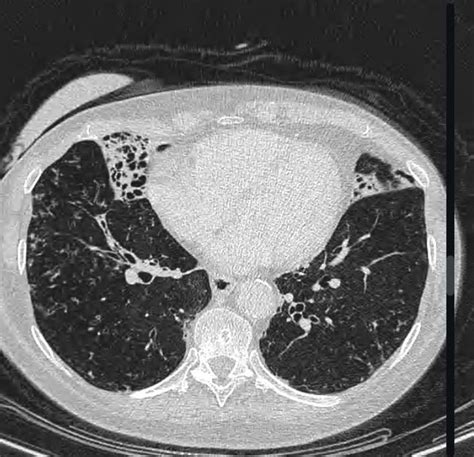

The syndrome was historically characterized in older women who chronically suppress their cough. By holding in their coughs to maintain social etiquette, these individuals inadvertently allow mucus, bacteria, and debris to accumulate in the airways of the lungs, specifically the right middle lobe and the lingula (part of the left upper lobe). This stagnation creates the perfect environment for NTM to colonize and cause chronic disease.

• High-Resolution Computed Tomography (HRCT) Scans: This is the gold standard for visualizing the characteristic bronchiectasis and nodules in the middle lobe and lingula.